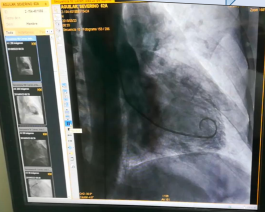

• Cineangiógrafo

Se instala en la sala N°2 de Hemodinámica un Cineangiógrafo Siemens, Intensificador de imagen de 9” que realiza proyecciones axiales y mejor definición de imágenes